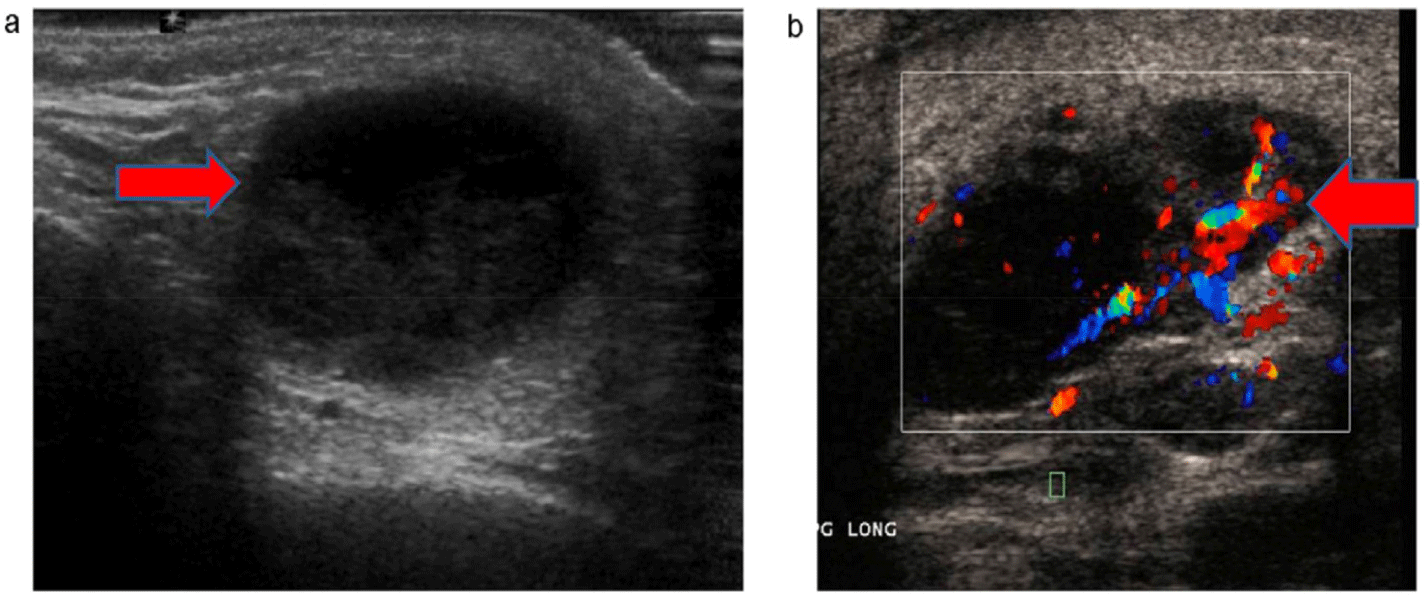

Imaging should be performed in the assessment of suppurative parotitis, especially in cases with suspected complications. Contrast-enhanced CT is particularly valuable for detecting large abscesses or identifying the spread of infection to adjacent structures, which is critical in patients at risk of developing mediastinitis or deep soft tissue infections. Moreover, ultrasound serves as a useful, non-invasive imaging modality to identify abscesses or fluid collections within the parotid gland, aiding in both diagnosis and management planning [37,38] (Figs. 2 and 3).